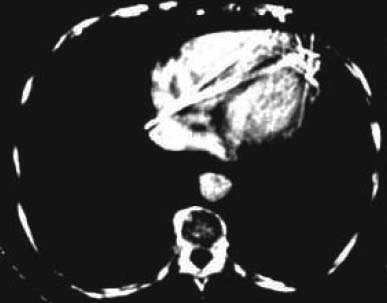

図8. 心電同期下に撮影された造影心臓CT.

ノーベル賞受賞講演では,スキャンジオメトリーについて解説されているが,商用機がまだ第2世代(translate-rotate方式)であったこの時点で,既に現在で第3世代(rotate方式),第4世代(stationary方式)について述べられている点には驚かされる(図7).また単に診断用途のみならず,治療計画における等線量図作成への応用が紹介され,将来展望として心臓CT,冠動脈CTについて触れ,心電同期造影心腔画像の例も紹介されている(図8).さらに当時まだ実用化されていなかったNMR撮影法 (MRI)について,その原理と特徴が相当な紙面を割いて紹介されている点も興味深い.CTとNMRは競合相手ではなく,将来的に共存し補完的な役割を果たすであろうと述べているところにも先見の明が感じられる.